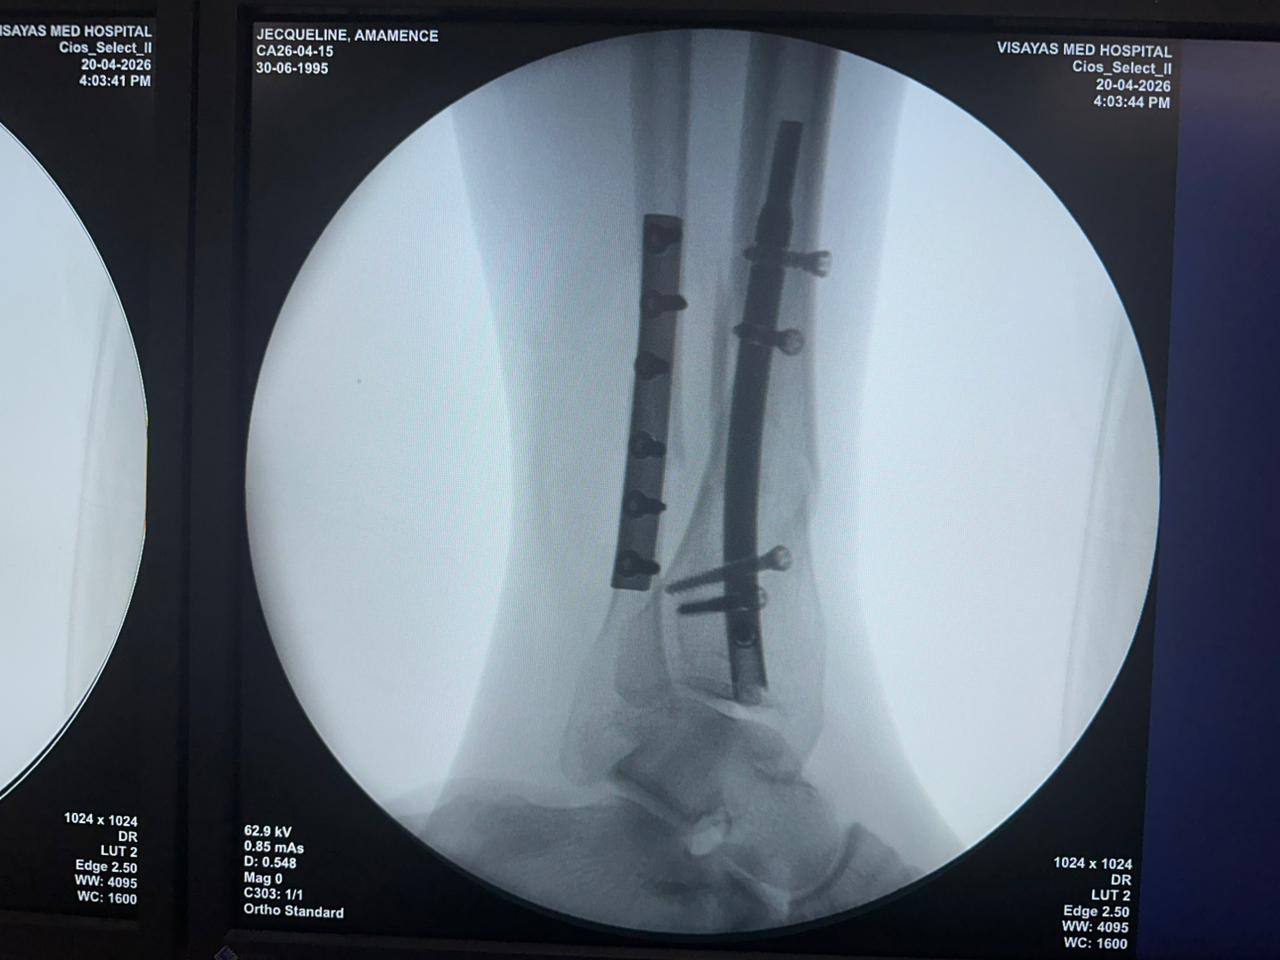

Caso di studio sulla fissazione del chiodo tibiale distale con supporto per placca peroneale

Fluoroscopia intraoperatoria con arco a C, viste AP e laterali

Questo caso prevedeva la fissazione tibiale distale utilizzando un chiodo tibiale distale intramidollare. La fluoroscopia intraoperatoria ha confermato la posizione del chiodo, delle viti di bloccaggio distali e della fissazione della placca peroneale.